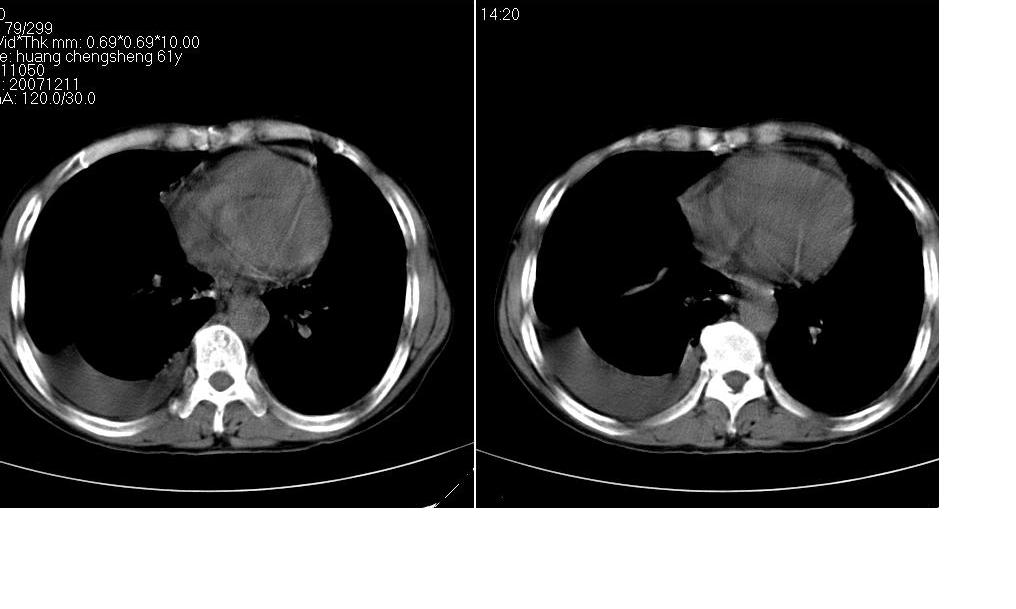

男 61岁,已确诊肺癌半年余.

右肺小细胞肺癌并纵隔淋巴结转移。胸腔积液,心包少量积液。左肺改变不除外癌性淋巴管炎

考虑:1、右肺下叶中心型肺癌并纵隔淋巴结转移。胸腔积液。

2、心包少量积液。

3、左肺改变不除外癌性淋巴管炎或化疗后肺间质纤维化。